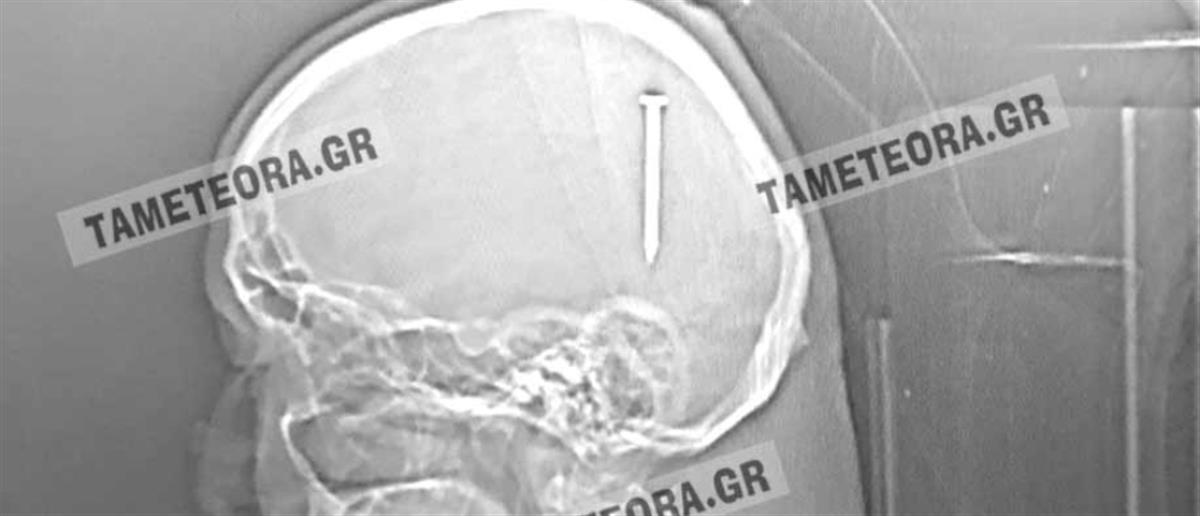

Καλαμπάκα: Του σφηνώθηκε καρφί στο κεφάλι! (εικόνες)

Από "θαύμα" σώθηκε ο άνδρας, ο οποίος βρέθηκε ξαφνικά με ένα καρφί στο κεφάλι του κατά την διάρκεια εργασιών.

Σύμφωνα με πληροφορίες, ο άνδρας βρέθηκε ξαφνικά με ένα καρφί 5 εκ. στο κεφάλι του κατά το διάστημα εργασιών που έκανε.

Εκτός από το αρχικό τράνταγμα που ένιωσε δεν ακολούθησε ούτε πόνος ούτε κάποιο άλλο σύμπτωμα.

Αρχικά μεταφέρθηκε στο Κέντρο Υγείας Καλαμπάκας, στη συνέχεια στο Γενικό Νοσοκομείο Τρικάλων και από εκεί στο Πανεπιστημιακό Νοσοκομείο Λάρισας, όπου του έγινε επέμβαση και του αφαιρέθηκε το καρφί με επιτυχία.

Ο άνδρας αναρρώνει υπό παρακολούθηση, αλλά εκτιμάται ότι δεν διατρέχει κανέναν κίνδυνο η υγεία του.

Πρόκειται πραγματικά για ένα σπανιότατο περιστατικό, καθώς αν το καρφί βρισκόταν ελάχιστα χιλιοστά από το σημείο που σφηνώθηκε, θα ήταν πολύ επικίνδυνο για την υγεία του.